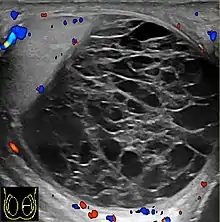

Primary leukemia of the testis is rare. However, due to the presence of blood-testis barrier, chemotherapeutic agents are unable to reach the testis, hence in boys with acute lymphoblastic leukemia, testicular involvement is reported in 5% to 10% of patients, with the majority found during clinical remission. The sonographic appearance of leukemia of the testis can be quite varied, as the tumors may be unilateral or bilateral, diffuse or focal, hypoechoic or hyperechoic. These findings are usually indistinguishable from that of the lymphoma [Fig. 9].

![Fig. 9. Leukemia. Diffuse hypoechoic infiltrative lesions are seen involving the whole testis, indistinguishable from that of the lymphoma.[citation needed]](../I/Scrotal_ultrasonography_of_leukemia.jpg.webp) Fig. 9. Leukemia. Diffuse hypoechoic infiltrative lesions are seen involving the whole testis, indistinguishable from that of the lymphoma.

Fig. 9. Leukemia. Diffuse hypoechoic infiltrative lesions are seen involving the whole testis, indistinguishable from that of the lymphoma.